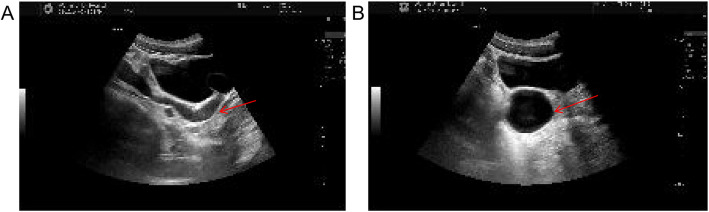

Case presentation: We report the case of an 18-year-old male presenting with urinary pain and was diagnosed with right renal agenesis and a left seminal vesicle cyst following comprehensive imaging. The patient also experienced perineal pain and urgency, without symptoms of frequent urination, dysuria, or hematuria, and no familial history of genitourinary anomalies was documented. He successfully underwent laparoscopic resection of a pelvic mass, with pathological examination confirming a seminal vesicle cyst. Postoperative recovery was uneventful. Whole exome sequencing of blood and tissue samples highlighted myeloma overexpressed gene (MYEOV), B melanoma antigen family member (BAGE), and N-acetylated-alpha-linked acidic dipeptidase 2 (NAALAD2) as potential mutated genes related to Zinner syndrome. Additionally, two predisposing genetic variants were identified.